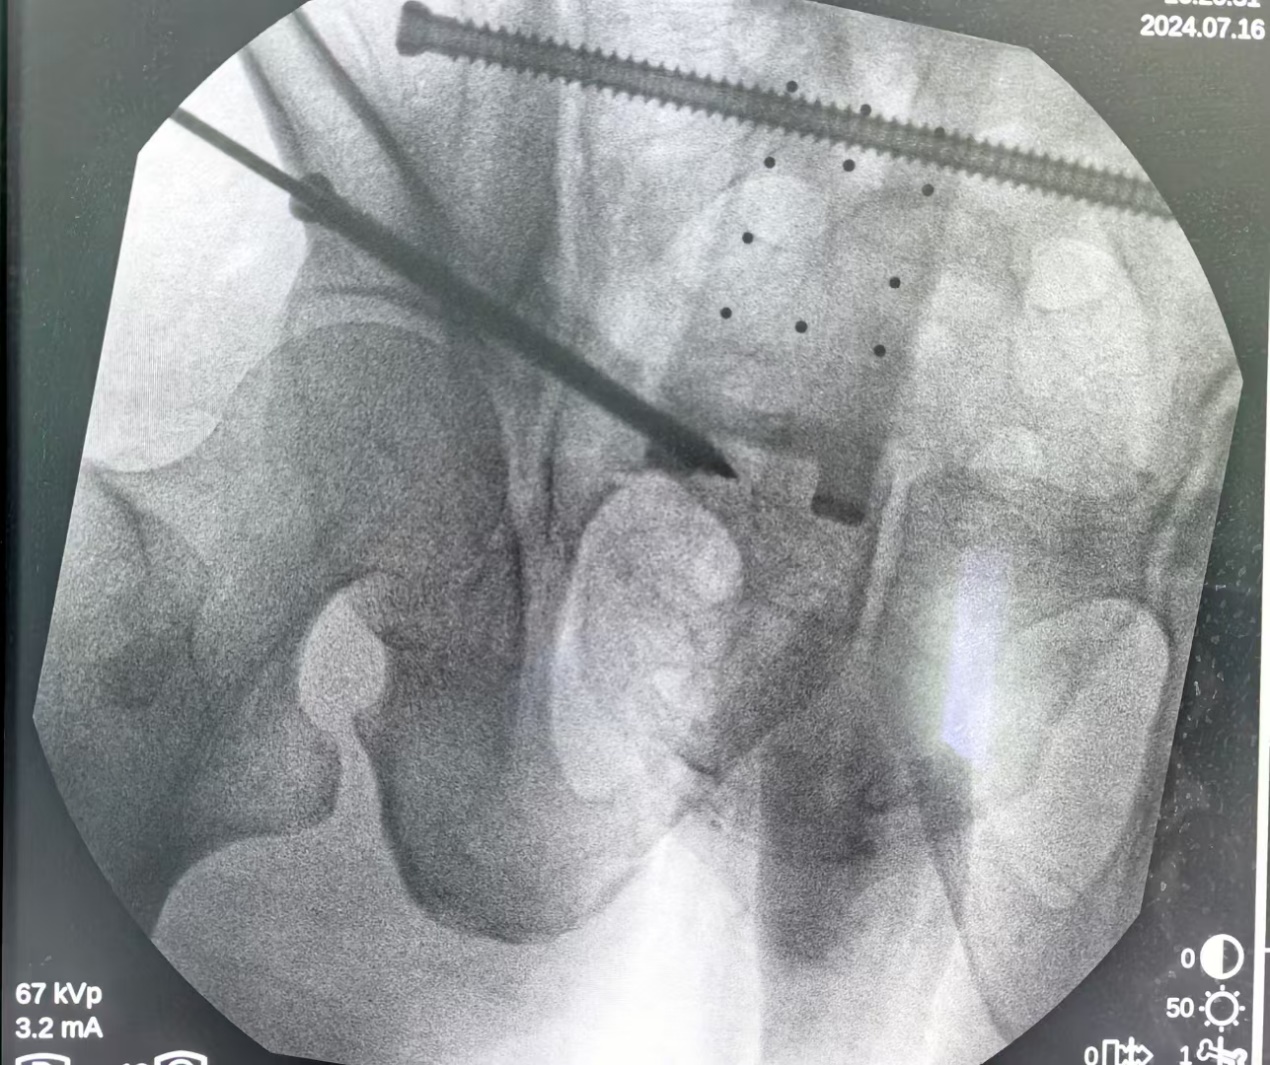

术中孙志波首先将定位追踪器安置在患者髂棘合适位置上,再把C型臂X光机透视所得患者骨盆影像资料导入手术机器人中,通过机器人自动化算法将影像图片与骨盆实体情况进行精准配对,并在显示器上规划好骶髂螺钉位置、长度以及角度,最后孙志波在定位套筒的导航下准确无误地将骶髂螺钉植入患者体内。术中全程通过机器人监视下调整角度,所有参数都经过算法精密推演,临床精度可达 0.1 毫米以内。从而可达到快速定位、精准植入、切口仅用1cm,术中出血量小,手术安全顺利。术后患者病情基本稳定,骨折所引起的疼痛已明显减轻。